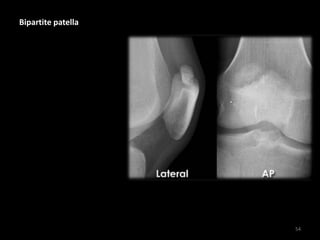

Bipartite patella

• The patella is bipartite

(in 2 parts) - a common

normal variant

• Note: Injury to the

interface of the 2

components is possible

which may be

symptomati